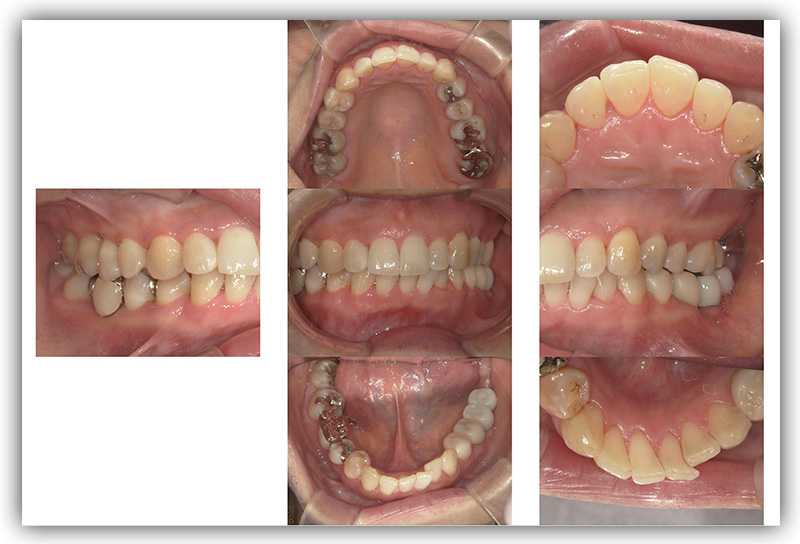

CASE_02

60代男性(インプラント)

- 患者さん情報(年齢・性別)

- 60代 男性

- 主訴

- 被せものが外れたところをインプラントにしたい

- 治療箇所

- 2箇所

- 治療方法

- インプラント

- 費用

- 約86万円

- 治療期間

- 約半年

- その治療によるリスク・副作用

-

- 治療期間がながい、外科的治療が必要

- 患者様の声